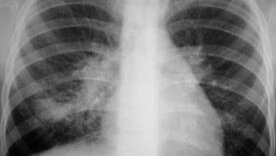

Флюорография, рентген и КТ органов грудной клетки : диагностика очагов в лёгких

Скрининговым методом выявления очагов в легких является флюорография, которую рекомендуют проходить ежегодно. Основная ее роль отводится к выявлению туберкулеза. Также при проведении флюорографии можно увидеть злокачественные образования лёгких и инфильтрацию при пневмонии...